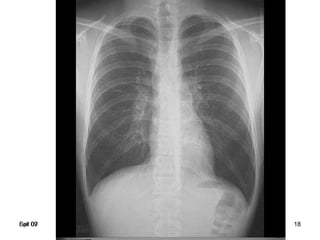

Spr 09 18Fall 07 18

Complete

right upper lobe

consolidation

Lobar pneumonia